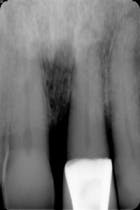

Fig. 3 Pericapical X-ray No. 9

When the patient first presented to the office, she showed normal periodontal measurements around all teeth with the exception of tooth No. 9. (Fig. 1) This tooth had an existing porcelain-to-metal crown that was in traumatic occlusion and with subgingival margins. (Fig. 2) The patient was scheduled to come in for treatment of No. 9; however, prior to that appointment she presented on an emergency basis due to a periodontal abscess associated with that same tooth. (Fig. 3). The tooth had 5 mm to 8 mm pocketing and mobility. Let’s consider the treatment options at this point: